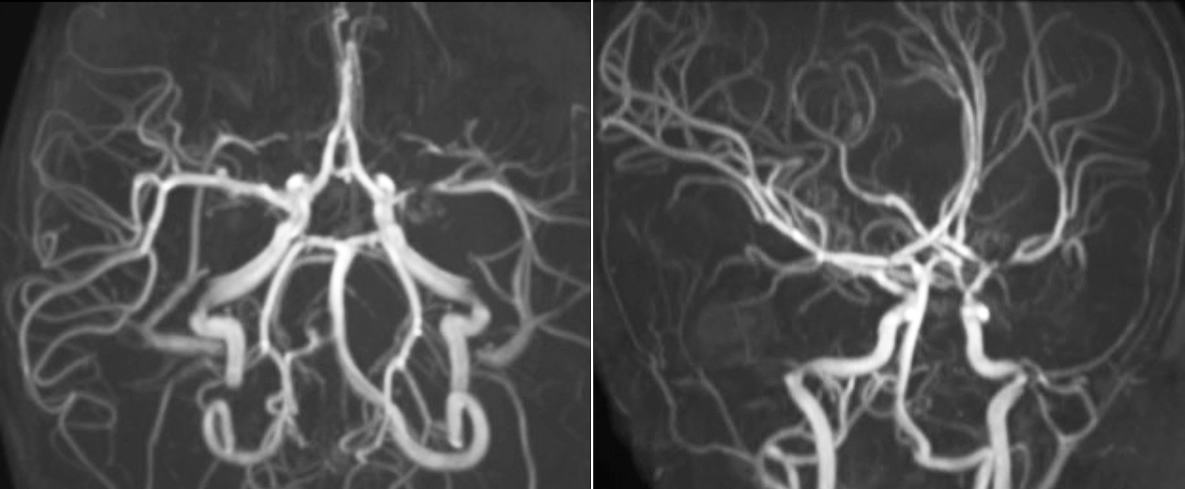

“A powerful use of pCASL is in patients with chronic cerebrovascular stenosis, where clinicians desire information on how compensatory mechanisms of the brain are performing to enable perfusion to the brain. Often clinicians take into account how the compensatory mechanisms appear to help to provide adequate perfusion to the patient’s brain, and they may intervene surgically or make some other management decision.”

“Another special application is the assessment of cerebrovascular reactivity with a Diamox perfusion exam, where we subtract two sets of pCASL images.”

Efficiencies gained with pCASL

“pCASL has now become more of a first-line scan for assessing perfusion for us, as opposed to DSC-based perfusion imaging with contrast agent. And in patients who were not planned to have contrast, we can perform pCASL for perfusion imaging without need to stop the exam, pull the patient out, and put in an IV. It also negates the postprocessing that’s necessary for dynamic susceptibility contrasts. And it allows us to repeat perfusion imaging in the same patient at the same imaging time, which is helpful in terms of patient motion, or in a situation where a scan needs to be done before pharmacological perfusion imaging.”